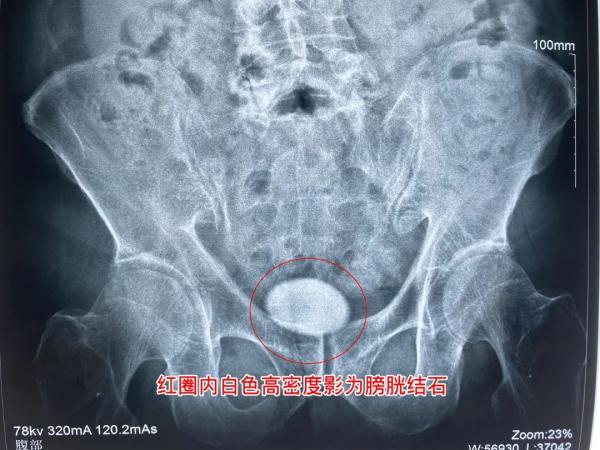

张先生术前腹平片检查结果局部图

9月15日,张先生到医院经过详细检查,确诊患有膀胱结石,且结石已达5公分,急需手术治疗。张先生便立即办理了入院手续。